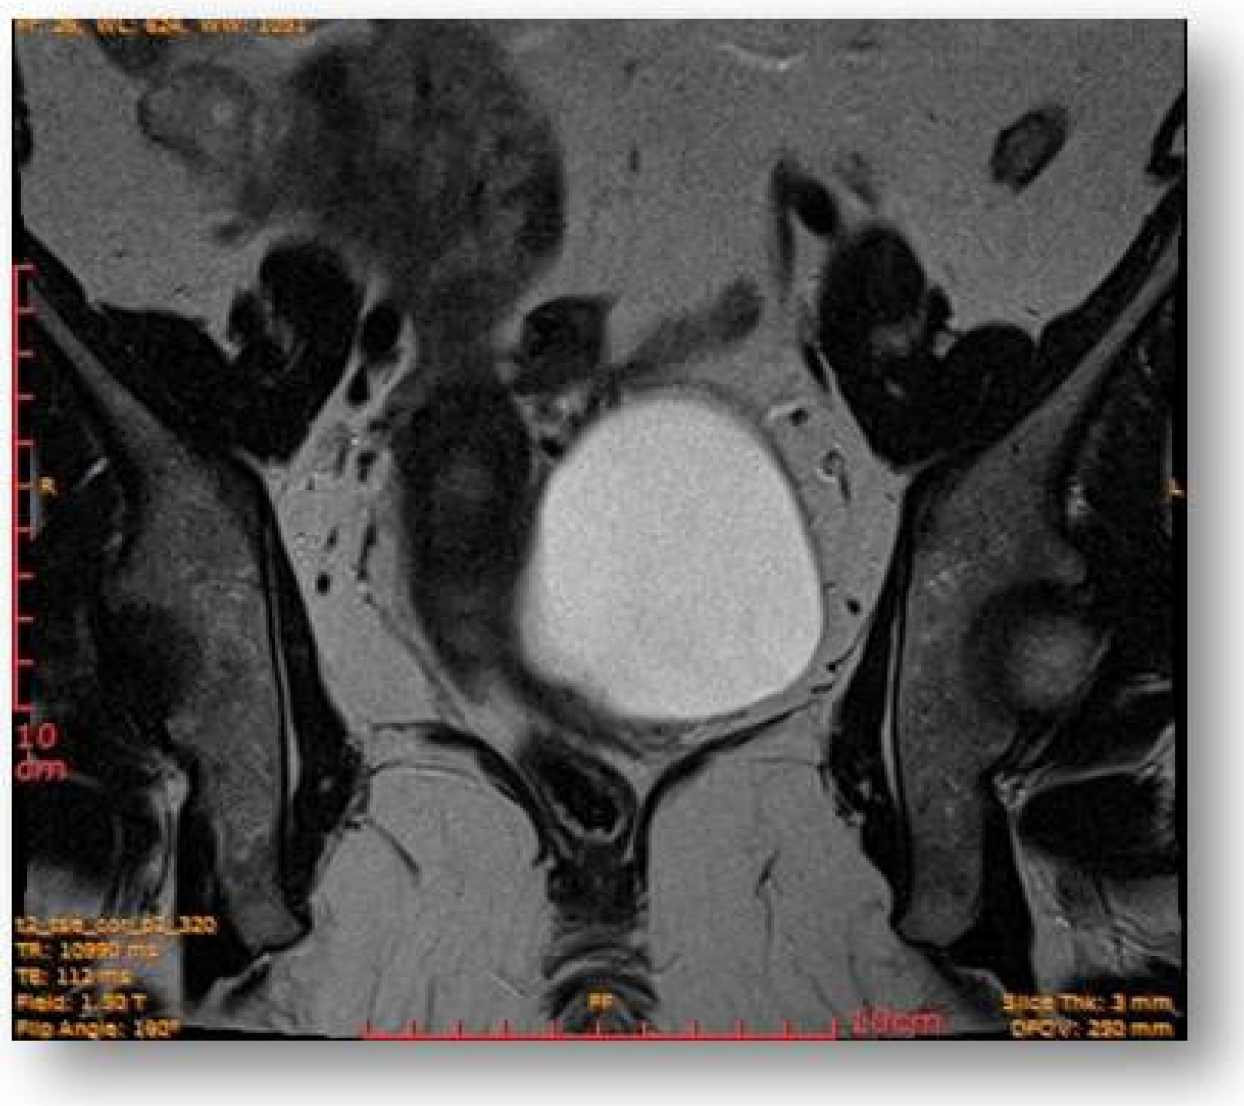

Considering all the information gathered, we first decided to perform an ultrasound (US) which revealed a large hypoechoic cystic formation on the left of the uterus, misdiagnosed as a paraovarian cyst measuring 80 mm (Figure 1, Figure 2, Figure 3 and Figure 4).

Figure 1.

Large hypoechoic cystic formation located to the left of the uterus measuring 80 mm.

Left parauterine, between the left lateruterine wall and the left ovary, was attached to the anterior contour of the uterine round ligament, and an ovoid cystic lesion of approximately 100/68/50 mm (oblique CC/AP/LL) is evident (Figure 5).

Figure 5.

Left parauterine, between the left lateruterine wall and the left ovary attached to the anterior outline of the round ligament, an ovoid cystic lesion of 100/68/50 mm is evident.

This showed probably proteinaceous fluid content and mildly irregular wall thickness up to ~4–5 mm (on the right lateral contour) and with a mural micronodule of ~5 mm with contrast uptake at the level of the left antero-lateral contour. The appearance advocated the first hypothesis for a “border-line” left paraovarian cyst, with suspicious elements of neoplastic transformation (Figure 6). It presented the following relationships: anteriorly, it imprints the anterior median-paramedian left pelvic wall, posteriorly with the uterine round ligament, urinary bladder, medially (to the right) with the uterus and urinary bladder, laterally (to the left) with the left ovary.

Figure 6.

Ovoid cystic lesion imprints the urinary bladder without invasion into it.

Ovoid cystic lesion proteinaceous fluid content and mildly irregular wall thickness up to ~4–5 mm.

Figure 8.

Ovoid cystic lesion in the left part of the uterus.